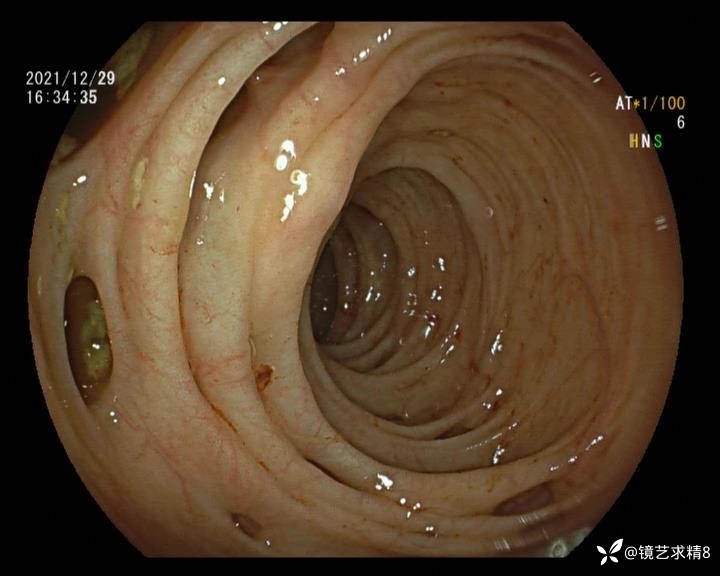

患者以消化道出血入院,胃镜未见异常,肠镜进入乙状结肠就看到很多憩室,同时还看到肠腔用清肠药后移动下来1枚尖锐的枣核,这么多憩室,这个枣核扎入憩室的机会非常大,推测应该是掉入一坑🕳就算出来还会有很多坑🕳🕳🕳等着,掉入憩室内很容易刺破血管,这可能就是消化道出血的原因,继续前进可以看到有一些憩室内翻,还有一些息肉,问题来了,那么多憩室,犯罪分子是抓住了,它在那些憩室内作过案?到达回盲部后挨个冲洗,但憩室大小又不足以把镜头进入憩室内观察,针对有血块的憩室冲洗后可疑出血的以夹子闭合或套扎,取出枣核,如果有锥形透明帽可能钻入憩室精准电凝效果更好,若内镜下操作失败介入治疗成功率更高,经内镜下治疗后观察未再出血出院。

亚洲人群结肠憩室主要发生在右半结肠,然后随着年龄的增长而延伸到左半结肠和双侧结肠。相比之下,欧美人群80%的结肠憩室好发于左半结肠,其中乙状结肠憩室占 70%,而大多是假性憩室。 然而,与憩室炎主要发生在左半结肠不同,东西方人群的憩室出血均主要发生在右半结肠,可能与右半结肠的憩室更宽大及憩室血管更易受到损伤相关。